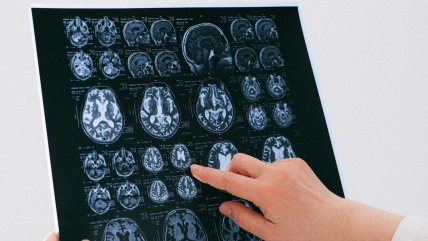

Las cinco etapas del cerebro humano: estudio revela cambios clave a los 9, 32, 66 y 83 años

Estudio descifró secretos de los "superancianos", octogenarios con cerebros de 50 años